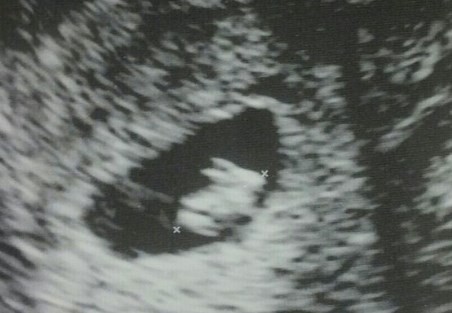

"Esta mañana fuimos a hacer la primera ecografía... Y resulta que voy a tener un conejo". La frase la escribió una usuaria anónima de Imgur para acompañar una imagen de la primera ecografía de su bebé en la que, como dice la futura mamá, más que un pequeño humano parece estar gestando un conejo.

La foto fue publicada el pasado viernes y, cuatro días después, ha recibido más de medio millón de visitas y acumula más de 60 comentarios. Muchos son los usuarios de Imgur que celebran el futuro nacimiento.